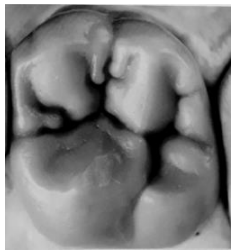

Enunciado 3941717-1

RIQUIERI, Hilton. Anatomia e Escultura Dental. Coleção APDESP. Ed.Napoleão.

Assinale a opção que indica o elemento dentário que corresponde à imagem acima.